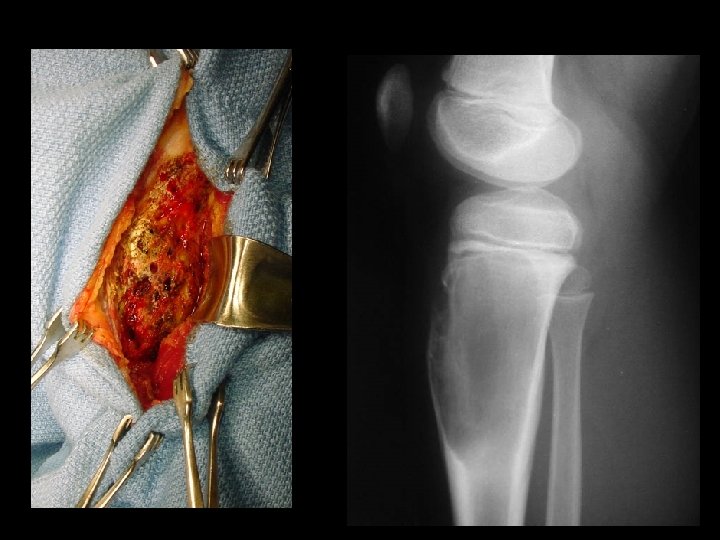

TREATMENT OPTIONS 1. Curettage & bone graft 2. Curettage & bone cement 3. Excision without replacement 4. Excision & replacement with: Artificial prosthesis (custom made) Allograft 5. Excision & replacement with upper end fibula 6. Excision & arthrodesis

Biopsy obvious superficial mass, blind biopsy • tissue compartments must not be • contaminated Biopsy should be done in consultation with a – tumor surgeon. skinny needle most helpful with metastatic • disease core best for primary tumor •

Giant cell tumour • • Uncertain origin Occurs in mature bone Area of old epiphysis Distal femur, proximal tibia, proximal humerus, distal radius.